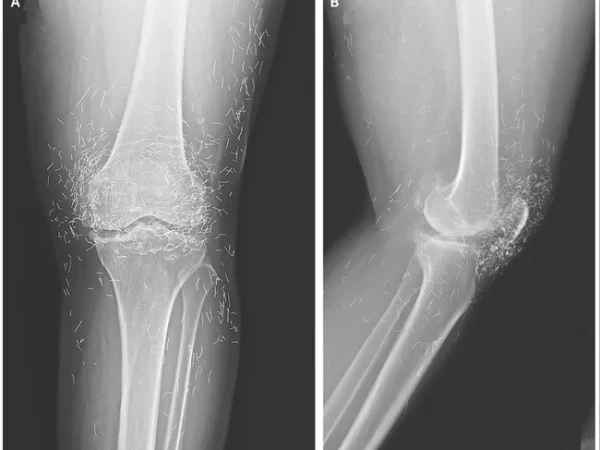

مذکورہ بالا تصویر ایک 65 سالہ خاتون کے گھُٹنے کے ایکسرے کی ہے جس میں دیکھا جا سکتا ہے کہ گھٹنے کے گرد سینکڑوں چھوٹے سونے کے تارموجود ہیں۔

بعد ازاں خواتین کے گھٹنے کا ایکس رے کیا گیا اور جو چیز سامنے آئی، وہ گھٹنے کے اندر سونے کے انتہائی باریک تار تھے۔ دراصل یہ تار اکیوپنکچر کے دوران باقاعدہ طریقے سے اندر چھوڑ دیے گئے تھے تاکہ جسمانی تحریکی اثر برقرار رہے۔

اگرچہ یہ طریقہ کچھ علاقوں میں آرتھرائٹس کے لیے استعمال ہوتا ہے، لیکن اس کے موثر ہونے کا کوئی مضبوط سائنسی ثبوت نہیں ہے۔ علاج مؤخر کرنے سے مناسب طبّی اقدامات میں تاخیر ہوتی ہے اور بیماری بڑھ سکتی ہے۔

مزید برآں سونے کے تار چھوڑنے سے سیسٹ بن سکتے ہیں، یہ جسم میں حرکت بھی کر سکتے ہیں اور ایم آر آئی جیسی تصاویر بنوانے میں رکاوٹ یا خطرہ پیدا ہو سکتا ہے۔